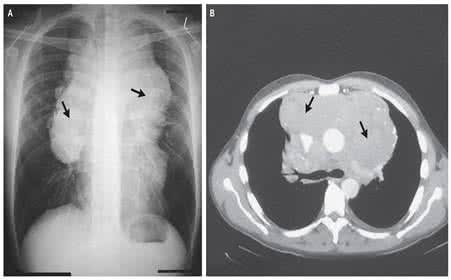

1.胸部影像学检查示双侧肺门及纵隔淋巴结对称性肿大,伴或不伴有肺内网状、结节状或片状阴影。

胸部影像学检查(X线胸片或CT)是必作的检查,有条件者应尽可能作肺活检,纤维支气管镜及支气管肺泡灌洗检查等以明确诊断,SACE、Kveim试验亦有一定诊断价值。